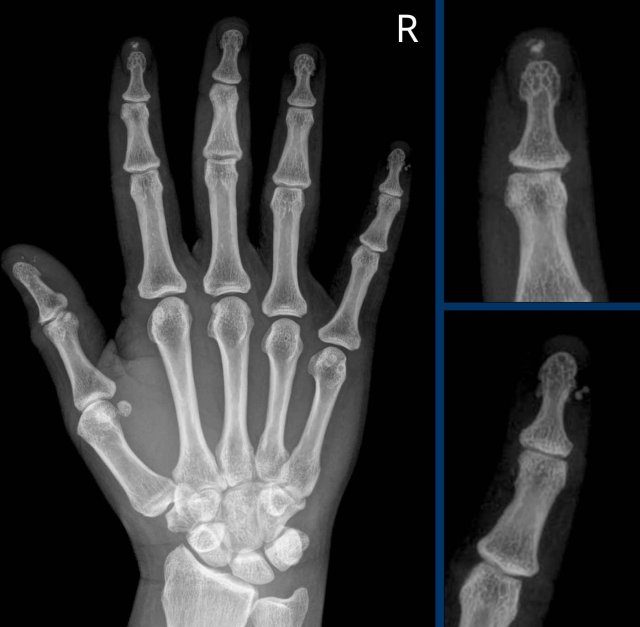

Sausage digits

Typical appearance of dactylitis “sausage digits” with soft tissue swelling and pencil-in-cup deformity of DIP 1-2 and 5 of the left hand in a patient with psoriatc arthritis.

Notice that the MCP joints are not involved (unlike in RA).

Progressive psoriatic arthritis

1. The picture on the left shows marginal erosions (black arrow) and subtle bone formation (blue arrow) of the IP joint.

2. Later on, it progresses to the typical pencil-in-cup deformation.

The distribution and the bone formation makes the diagnosis of rheumatoid arthritis unlikely.

The marginal erosions and the absence of DIP involvement in other joints makes the diagnosis of erosive osteoarthritis unlikely, although pencil-in-cup can look like the gullwing deformity in erosive osteoarthritis.